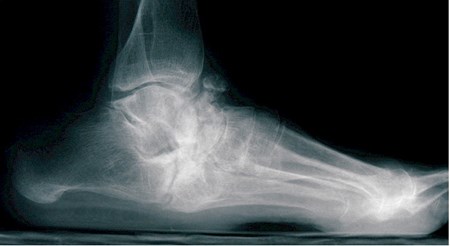

- Eerst is er de fragmentatie of destructiefase. In dit stadium gaan het gewricht en het omgevende bot kapot. De botfragmenten en het gewricht worden onstabiel, en in sommige gevallen verdwijnt het bot volledig door absorptie. De eerste fase geeft opvallend veel zwelling (vaak met weinig pijn), roodheid (erythema), en warmte. Door dit fenomeen is het gemakkelijk te begrijpen dat de eerste fase van Charcot arthropathie verward wordt met een diepe infectie, vooral omdat er vaak geen sprake is van een letsel of trauma. Tijdens de bot- en gewrichtsaantasting, ontwikkelen zich breuken en instabiliteit waardoor de gewrichten kunnen ontwrichten of de botten zich kunnen verplaatsen ten opzichte van elkaar. Dit kan leiden tot ernstige misvorming van voet en enkel. De middenvoet wordt vaak aangetast, waardoor een heel platte voet ontstaat die breed is waar een normale voet vernauwt in zijn voetboog. Er ontstaan vaak benige uitsteeksels op het steunvlak van de voet. Diagnose en vroege behandeling in dit eerste stadium zijn heel belangrijk om te proberen de botdestructie en de misvorming minimaal te houden. Deze eerste fase kan zelfs 6 tot 12 maand duren.

- Eenmaal het acute proces is verdwenen en de heling is ingezet, begint de derde fase. Dit is de consolidatie- of reconstructiefase tijdens dewelke het bot en de gewrichten genezen. Jammer genoeg is ondertussen de voet vaak al misvormd, en als er genoeg vernietiging is opgetreden, kan er blijvende instabiliteit zijn. Schoenaanpassing wordt dan vaak heel moeilijk, en op maat gemaakt schoeisel en diabetische inlegzolen zijn belangrijk om vormen van ulcera boven misvormde zones te helpen voorkomen.